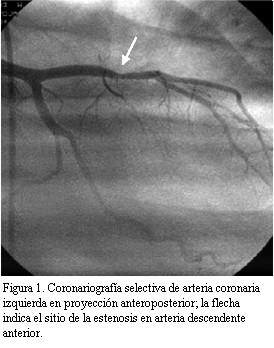

En buen estado de salud en marzo de 2004 (seis años y ocho meses después del TxC), instala astenia, adinamia y disnea clase funcional II-III (NYHA). Se realiza ecocardiograma transtorácico que mostró severa disminución de la FEVI. Se realizó cineangiocoronariografía (CACG) comprobándose lesión severa (75%) excéntrica del sector medio de arteria descendente anterior luego del origen de primera septal. Sector distal sin lesiones (figura 1). Se realiza angiograplastia transluminal coronaria (ATC) con implante de stent con sirolimus (Cypher) en forma primaria para arteria descendente anterior (figura 2). La estenosis residual fue 0%. La arteria descendente anterior presentó después de la ATC flujo TIMI III.

Buena evolución posterior con mejoría de la clase funcional, así como de la contractilidad ventricular izquierda en ETT de control.